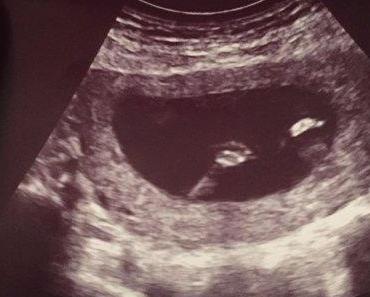

{Schwangerschaft #2} Woche 20

Feb. 20, 2016